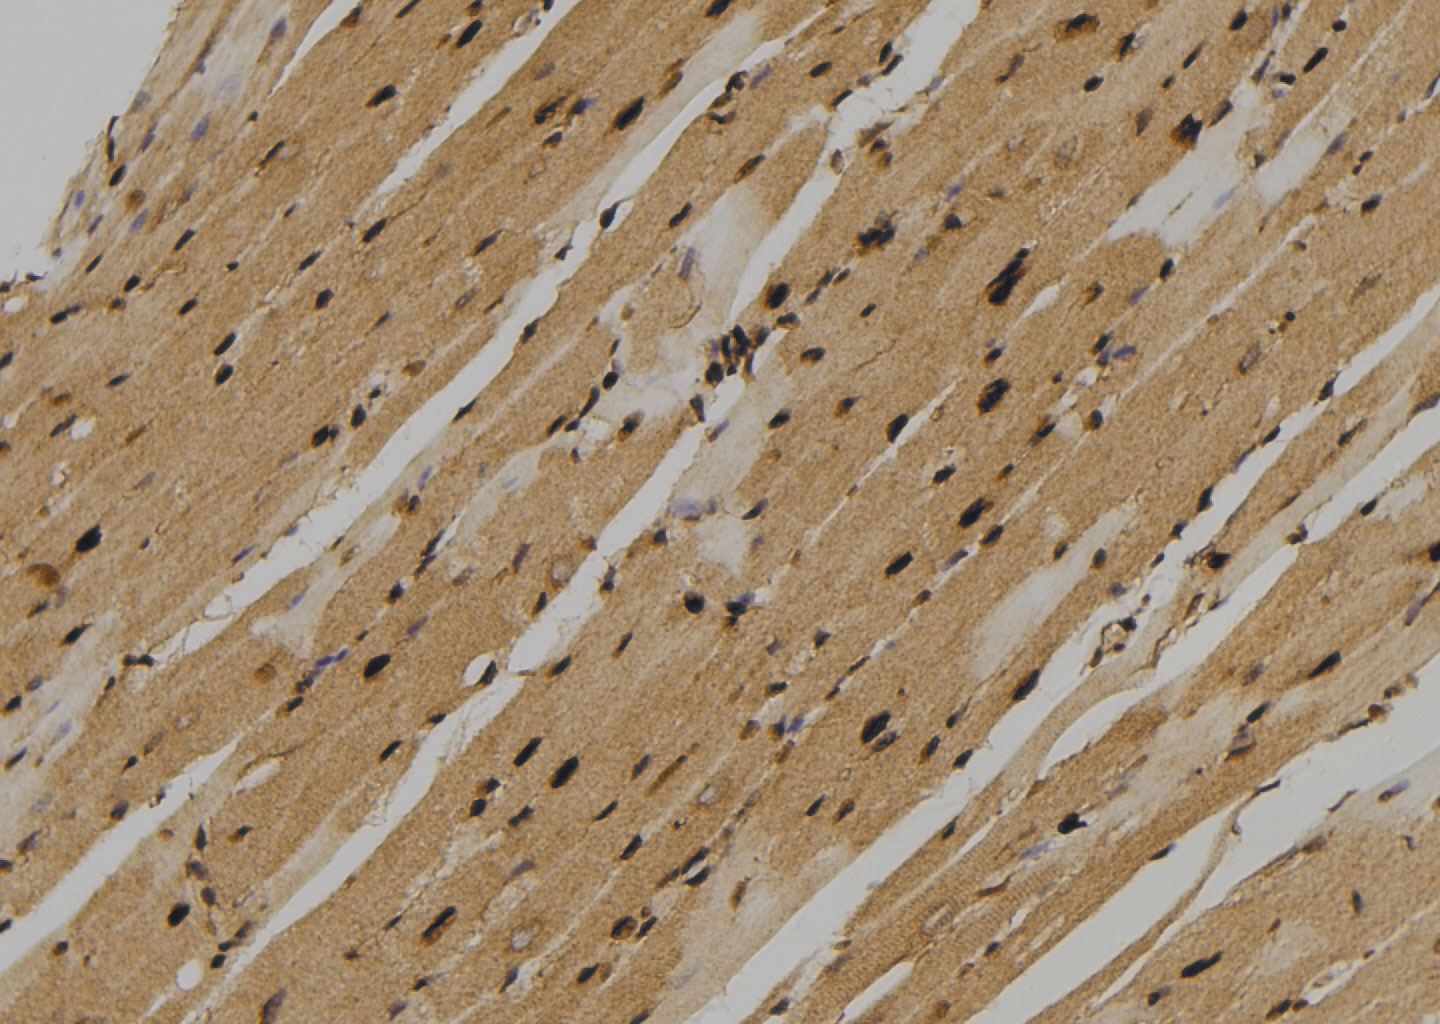

IHC-P analysis of mouse heart tissue using GTX00795 TIE2 (phospho Tyr897) antibody.

Antigen retrieval : Heat mediated antigen retrieval step in citrate buffer

Dilution : 1:100